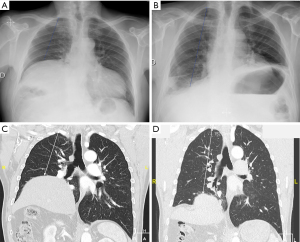

The following parameters were collected from the medical records at diagnosis: age, sex, body mass index (BMI), American Society of Anesthesiologists (ASA) physical status score, medical history: arrhythmia, coronaropathy, chronic obstructive pulmonary disease (COPD), pulmonary embolism, previous thoracic or cardiac surgery, smoking behavior, symptoms related to UDP. Evaluation of MRC was performed by the practician during the pre-operative consultation, according to the level of exercise possible for patients (from strenuous exercise to dressing). All radiologic exams were reviewed by an expert thoracic radiologist. Distance from apex (the upper edge of the first rib) to the top of the diaphragmatic dome [distance from apex to diaphragm (A-D)] was measured on chest X-ray in inspiration and on CT (in a coronal view at the carina level, 5 mm thickness in parenchymal window) (Figure 1). These static measurements were recorded pre-operatively. From pulmonary spirometry, we recorded pre-operatively, in sitting position: forced expiratory volume in one second (FEV1), VC, total pulmonary capacity (TPC) and residual volume (RV) and in supine position only VC. During hospitalization, the following parameters were collected: surgical technique, length of surgery, per-operative complication(s), time to chest tube ablation, length of hospital stay, incidence of complications before hospital discharge or in the 90 days after surgery according to the Clavien-Dindo classification. During follow-up, we recorded: clinical evaluation of dyspnea according to MRC dyspnea scale spirometry data, measurements on chest X-ray and measurements on CT. Patients lost to follow-up after their first post-operative consultation were contacted telephonically and invited to come for a consultation at our institution, where dyspnea score and clinical evaluation were done. Chest X-ray, CT and spirometry were performed during this consultation. Median time of follow-up was 19 months.

On chest X-ray (Figure 5) we observed a statistically significant augmentation of the distance A-D from 12±3.2 cm at diagnosis to 19±2.8 cm at 6 months (P=0.001). These results were persistent at last follow-up with an A-D distance at 17.9±3.59 cm (P=0.001), and no recurrence of diaphragmatic eventration was observed. This improvement was similarly found on CT with an increased distance A-D from 10.3±2.68 cm at diagnosis to 16.3±2.6 cm (P=0.001) at last news. Median time to last evaluation of measurement on chest X-ray and CT was 20 months. There was no statistically significant correlation between the distance A-D on chest X-ray and VC measurements in sitting position (correlation coefficient was 0.406, P=0.055) or in supine position (correlation coefficient was −0.508, P=0.09), but there was a statistically significant correlation between the distance A-D and dyspnea with a correlation coefficient of −0.578 (P=0.004).